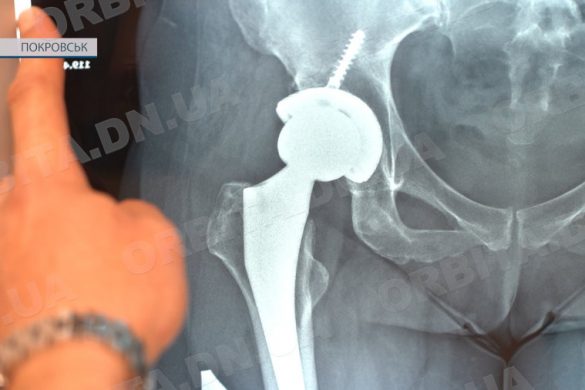

У Покровській КЛІЛ проводять унікальні операції з ендопротезування

22.02.2024, 19:46 0 комментариев52Ендопротезування – це операції із заміни суглобу. У Покровській КЛІЛ їх проводить Віталій Михаленко, котрий має чималий стаж роботи, а у 2015 році був удостоєний звання «Заслужений лікар України». У нашому медзакладі він трудиться з…